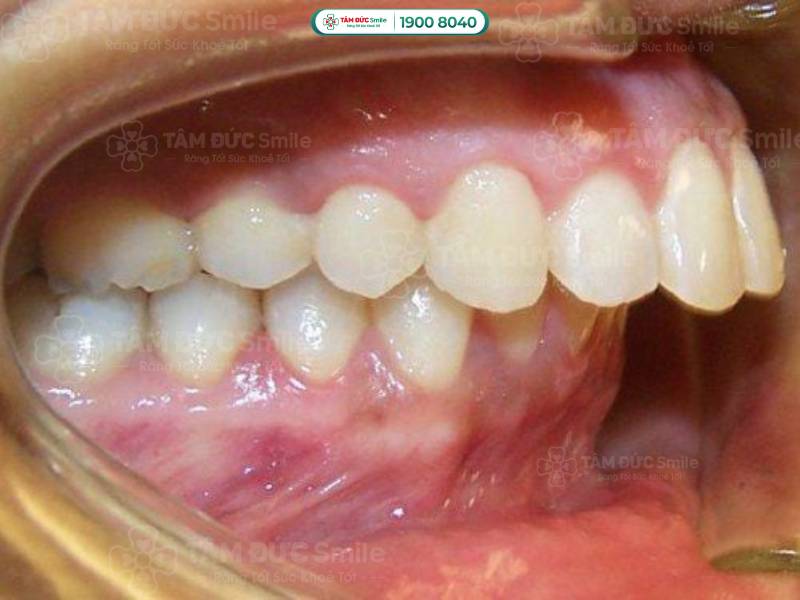

Khớp cắn sâu là tình trạng sai lệch cấu trúc răng và xương hàm. Khi đó, hàm dưới bị lệch về phía sau so với hàm trên và bị hàm trên che khuất.

- Hàm dưới bị lệch về phía sau so với hàm trên, hình thành một khoảng cách giữa răng trên và răng dưới.

- Răng hàm dưới bị răng hàm trên che khuất. Răng hàm dưới có thể chạm vào phần nướu trong của răng hàm trên.

Khớp cắn sâu là tình trạng hàm dưới bị lệch về phía sau so với hàm trên và bị hàm trên che khuất